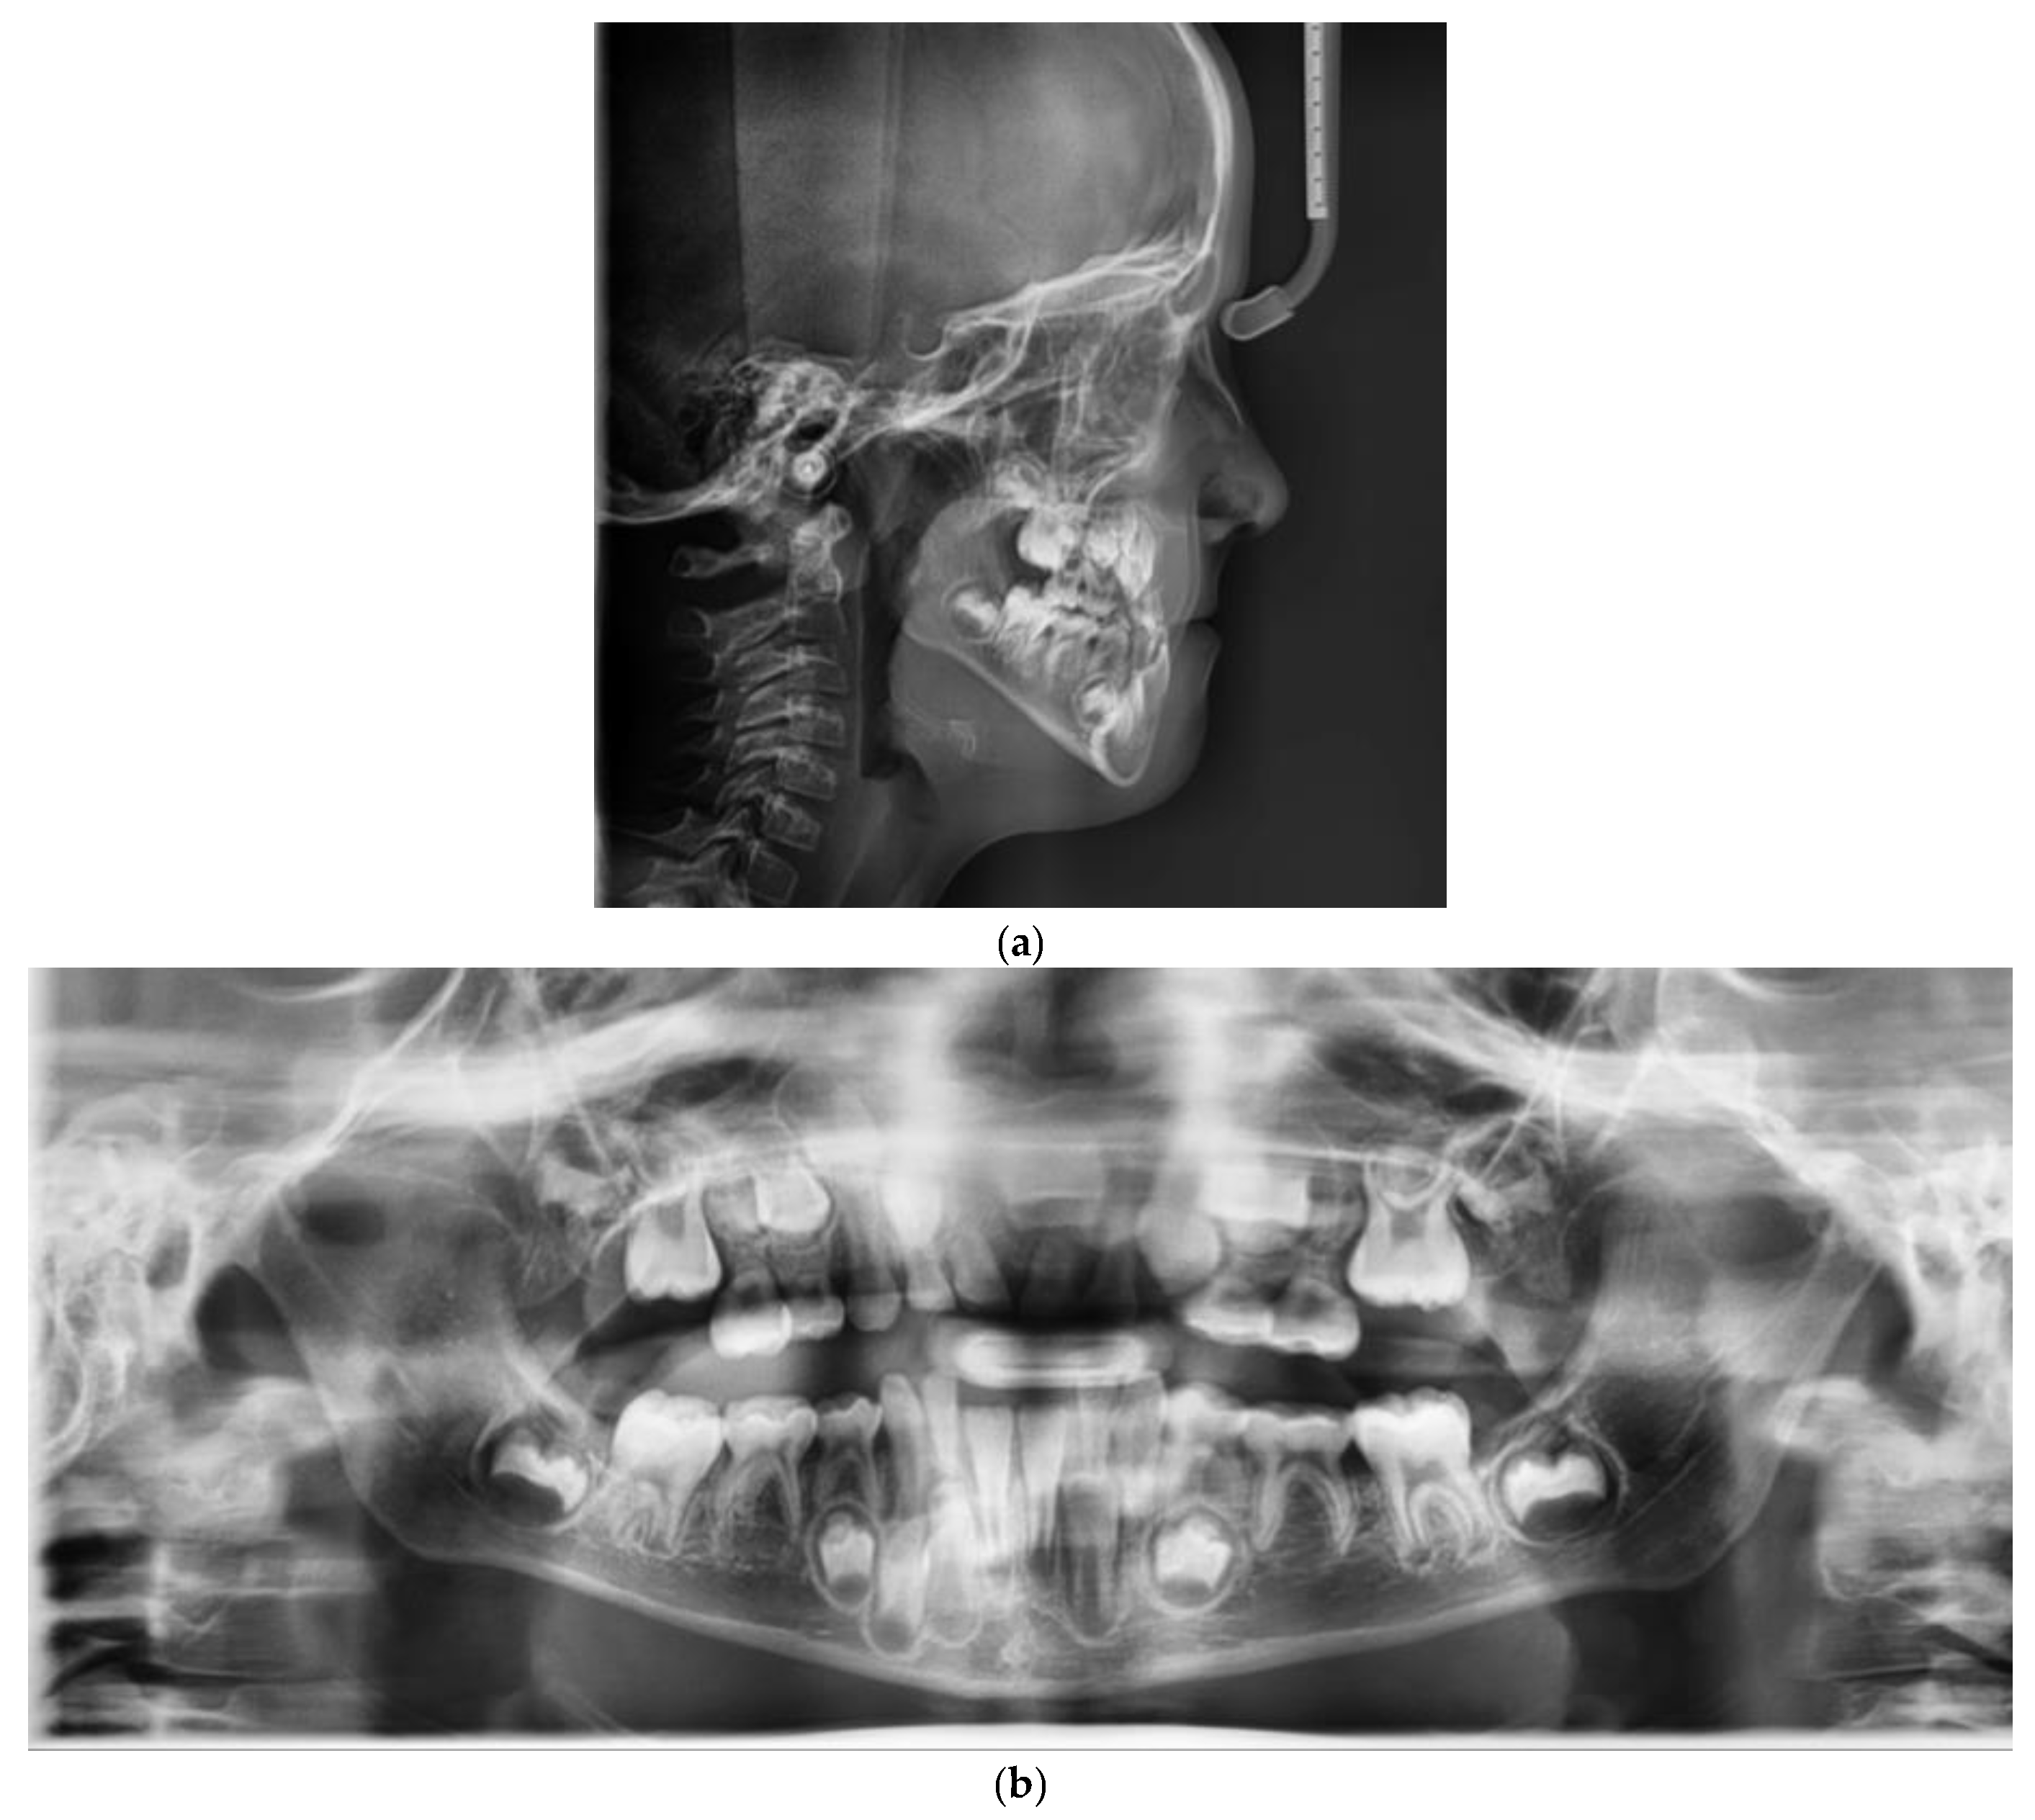

2. Case Report

4. Treatment Progress